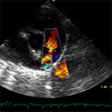

Transposición completa de las grandes arterias En esta lesión, la aorta se origina en el ventrículo derecho, a la derecha y delante de la arteria pulmonar, que se origina en el ventrículo izquierdo. Esto provoca la existencia de dos circulaciones separadas y paralelas, izquierda por lo que es indispensable que exista una comunicación entre ambas después del nacimiento para la supervivencia....

Transposición completa de las grandes arterias En esta lesión, la aorta se origina en el ventrículo derecho, a la derecha y delante de la arteria pulmonar, que se origina en el ventrículo izquierdo. Esto provoca la existencia de dos circulaciones separadas y paralelas, izquierda por lo que es indispensable que exista una comunicación entre ambas después del nacimiento para la supervivencia.... -